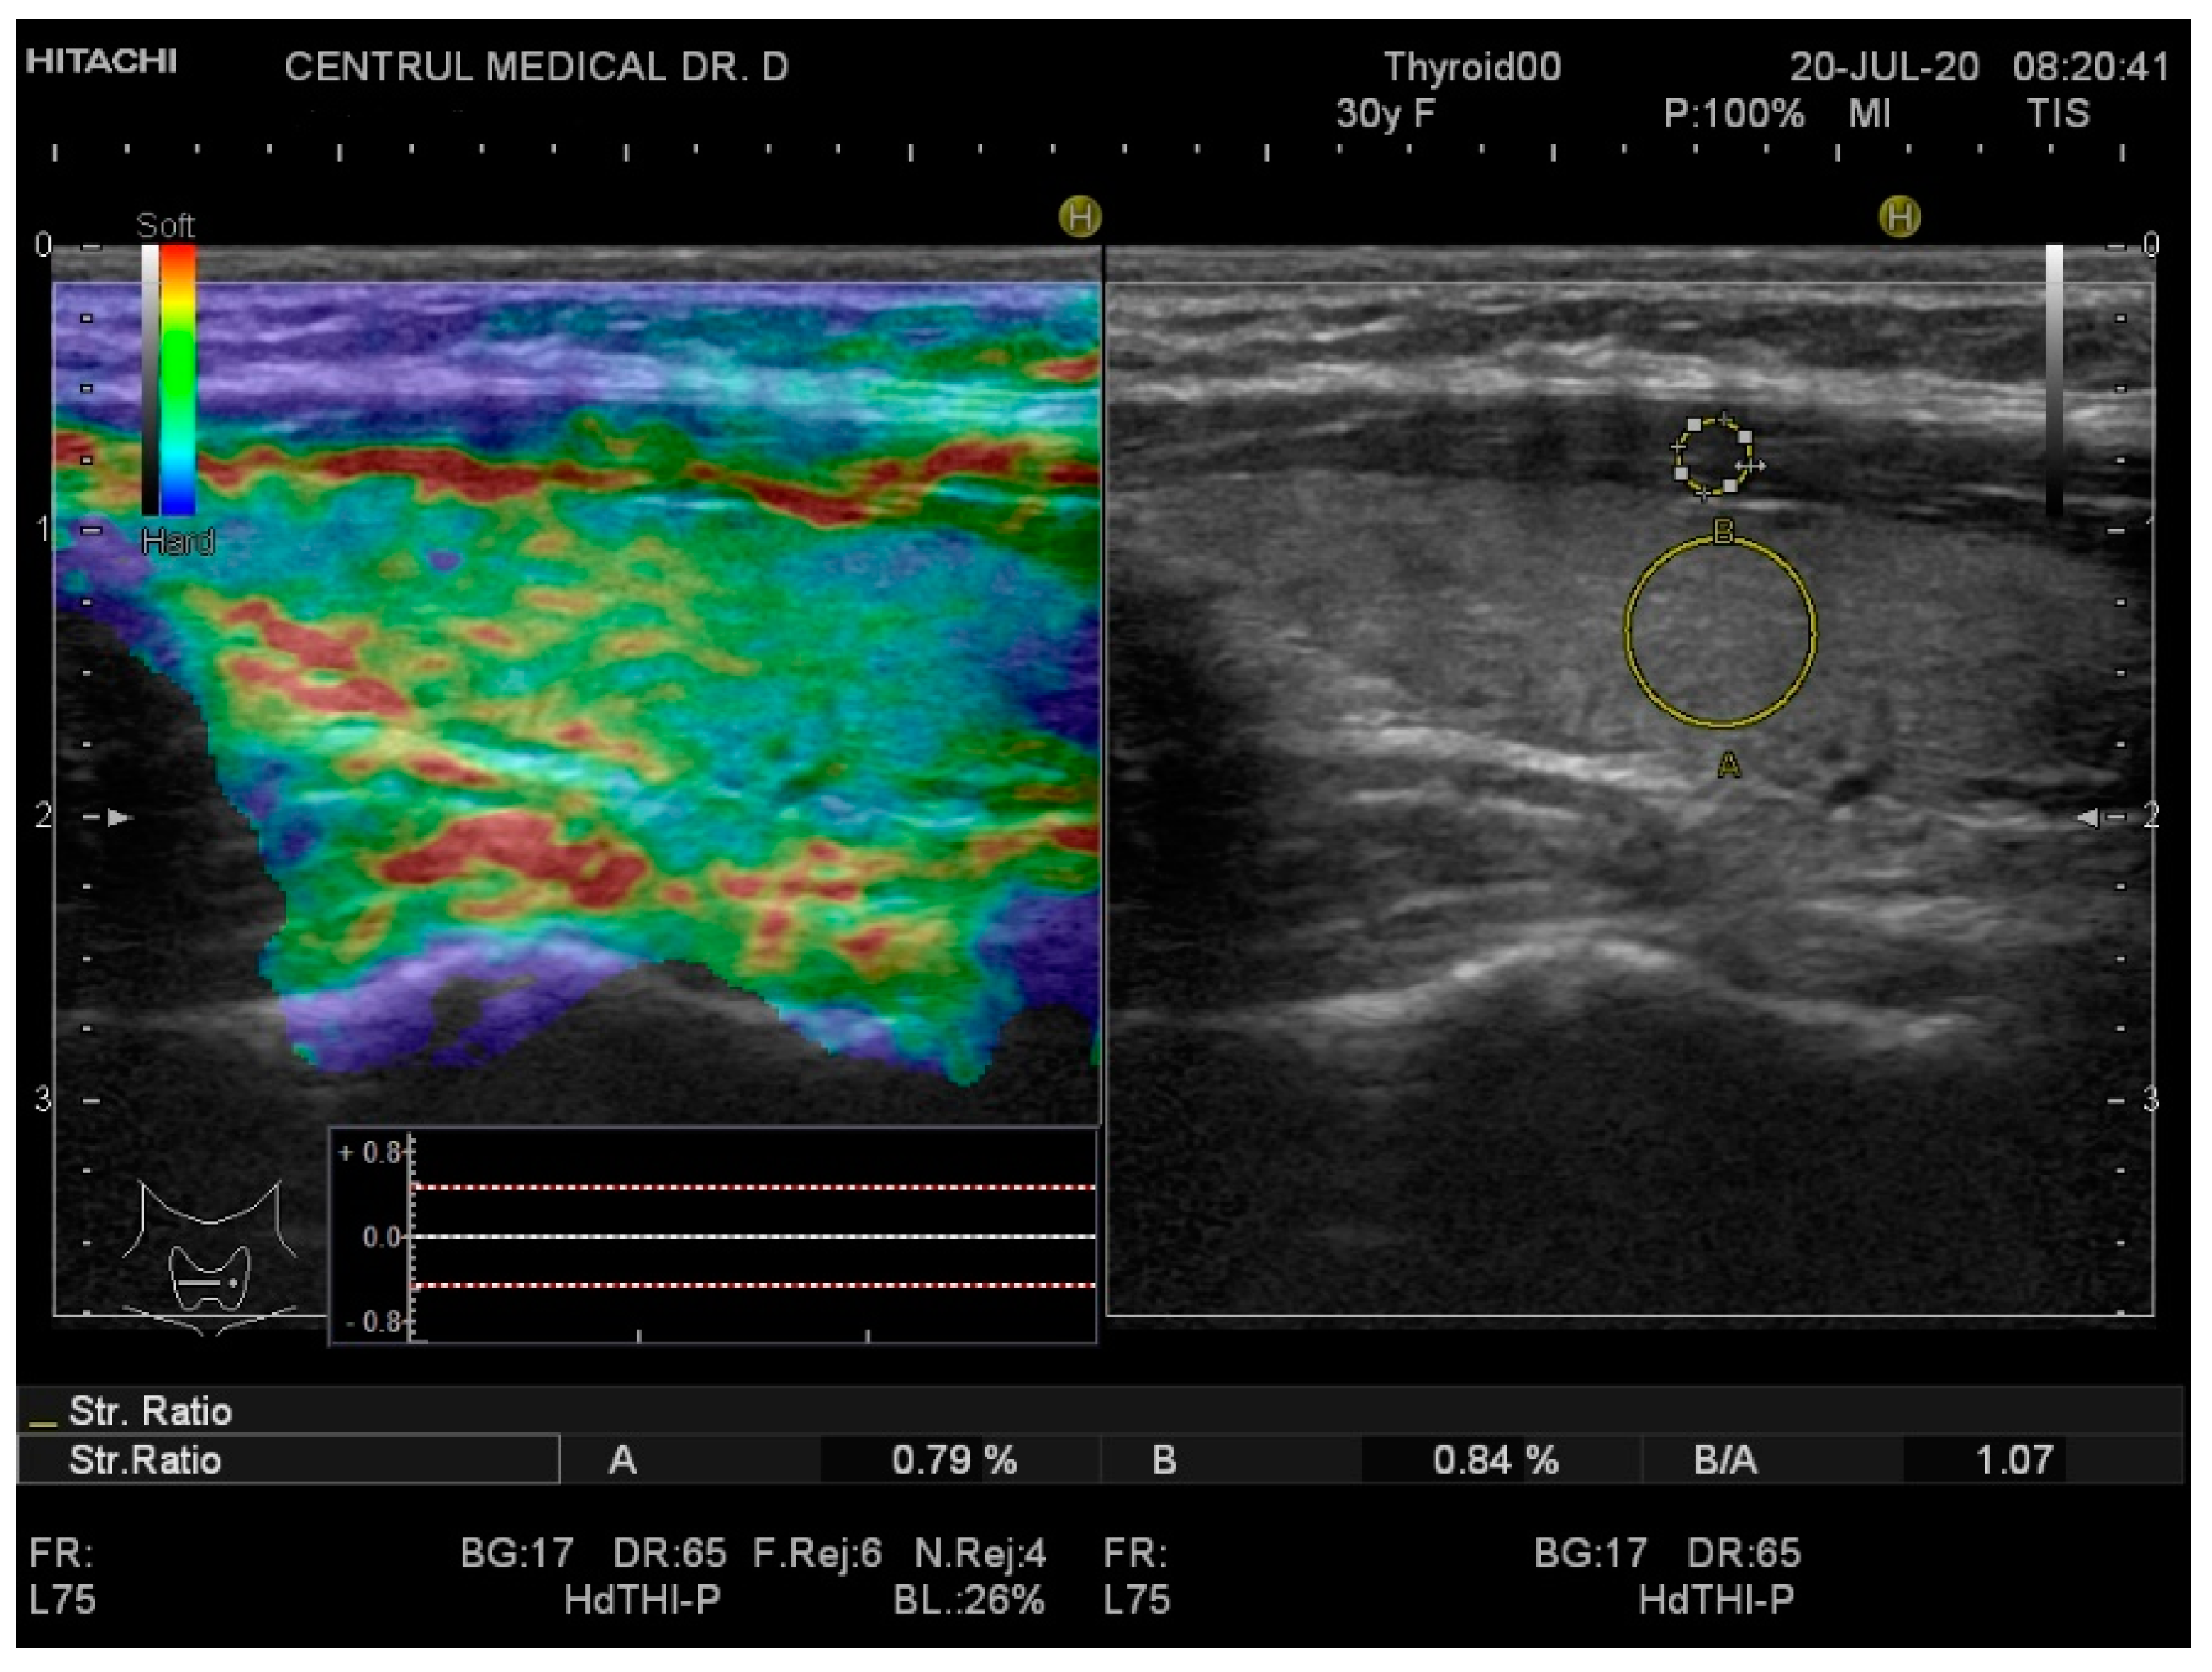

Real-time elastography was performed after conventional US during the same visit. The stiffness measurements were collected in the same session as the grey-scale US evaluation. The probe was placed perpendicularly to the skin and repetitive, light compression was applied avoiding lateral movement. All images were obtained in the longitudinal plane. A blue-green-red color map was displayed with blue indicating no strain (high stiffness), green indicating intermediate stiffness and red representing soft tissue. In order to calculate the strain ratio (SR), two regions of interest (ROI) were placed consequently. The first one, ROI A, was the thyroid tissue while the second one, ROI B, was the sternocleidomastoid muscle in front of the ipsilateral thyroid parenchyma. Figure 1 and Figure 2 below illustrate the SE image and calculation of the SR in normal thyroid tissue and, respectively, in a patient with CAT. Five consecutive measurements were made for each lobe and the mean value was considered in the final evaluation. The SR was calculated and displayed automatically for each lobe.

Figure 1.

Strain elastography (left) and grey-scale ultrasound (US) (right) of a healthy patient—left thyroid lobe. The yellow circle A is the local region of interest (ROI) on the thyroid tissue; the yellow circle B is the local ROI on the sternocleidomastoid muscle adjacent to the thyroid. Strain ratio (SR) = 1.07.